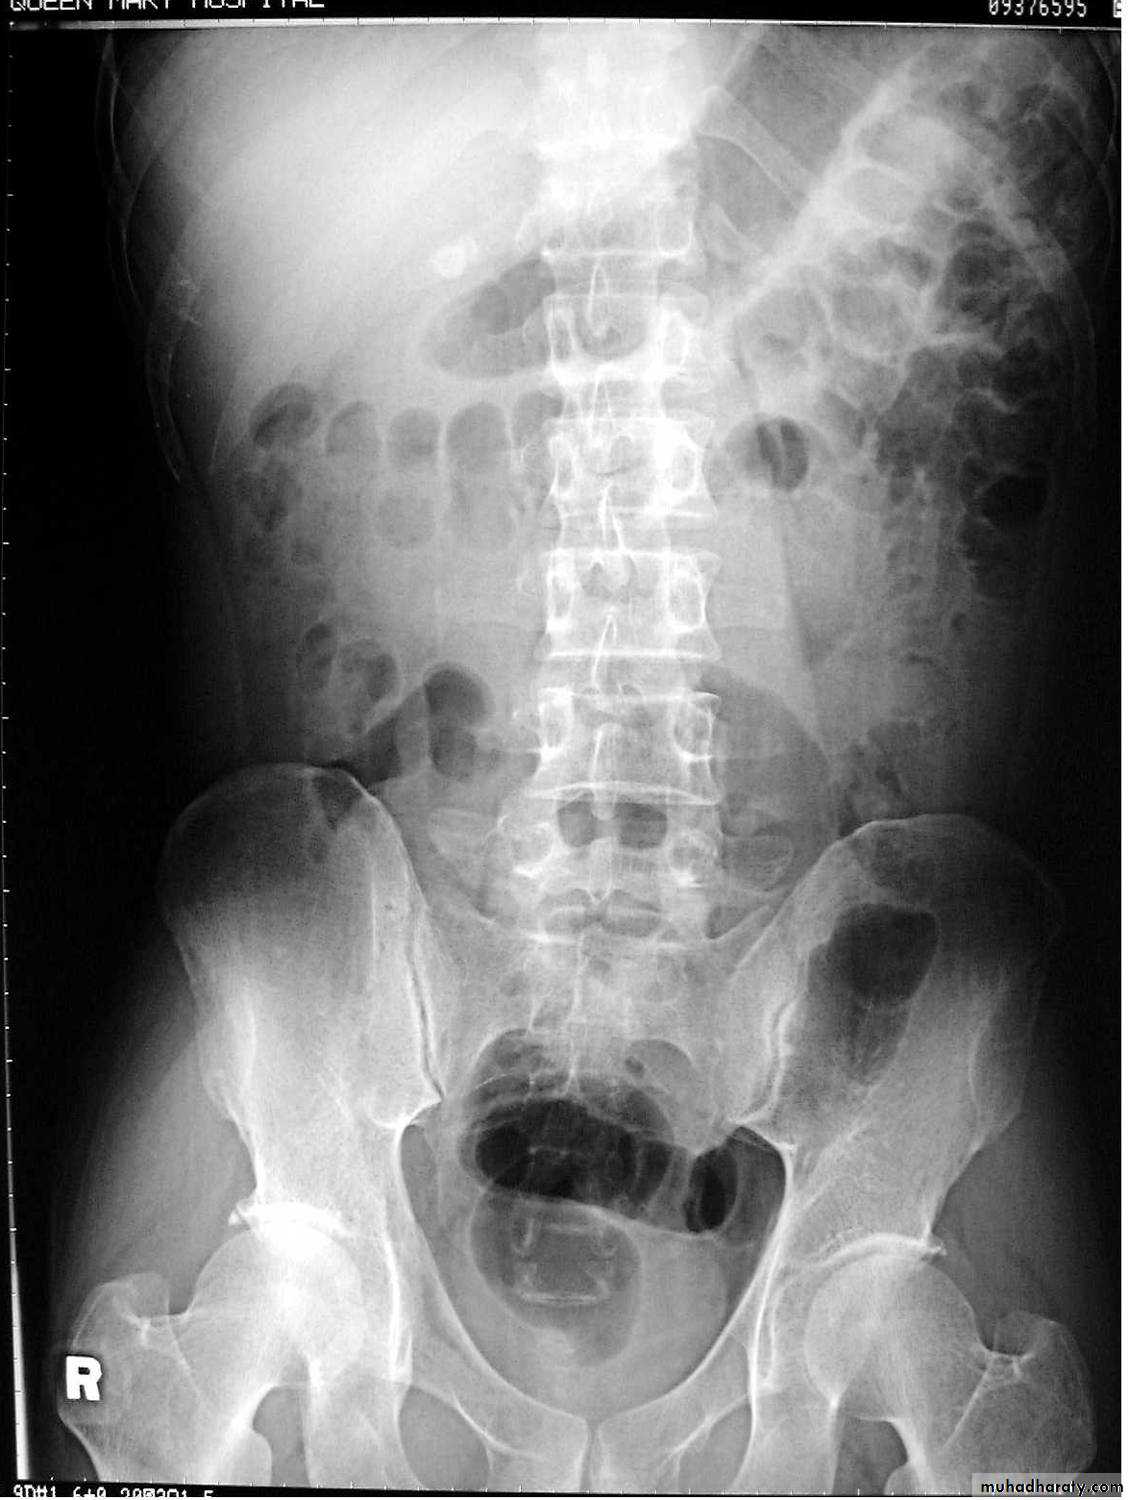

UC

The colon is distended with air

The descending & sigmoid colon are featureless (no haustral pattern)

•

Thumb printing